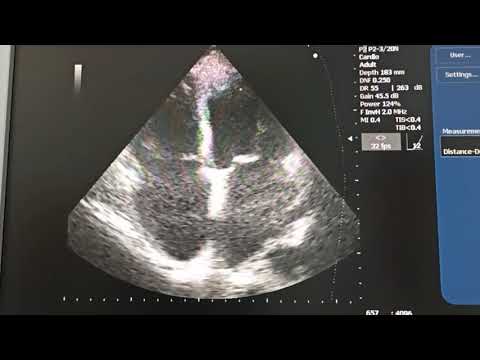

S40Exp 9 Кардио расчеты

Эхокардиография. Разбор случая с АОРТАЛЬНЫМ СТЕНОЗОМ, низкой ФВ, ФП, ДИЛАТАЦИЕЙ всех полостей.

Оценка легочной артерии правого желудочка и предсердий у пациента с фибрилляцией предсердий

Оценка диастолической функции левого желудочка (д.м.н. Шульгина Л.Э.)

Мастер класс по ультразвуковой диагностике в эхокардиографии